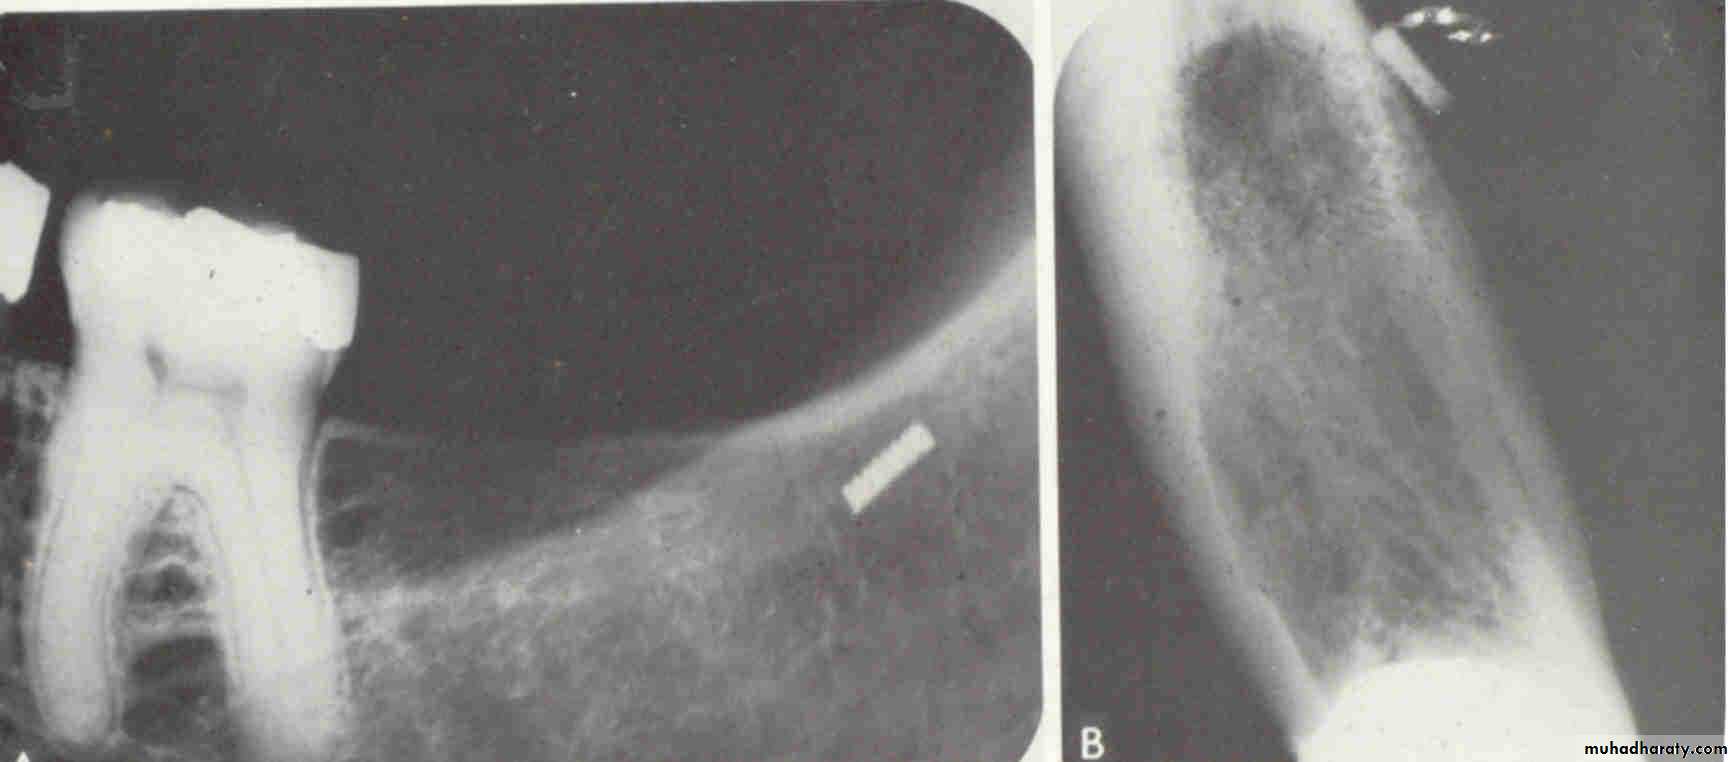

FOREIGN BODYWATERS VIEW(Occipitomental )

LATERAL VIEWLateral oblique